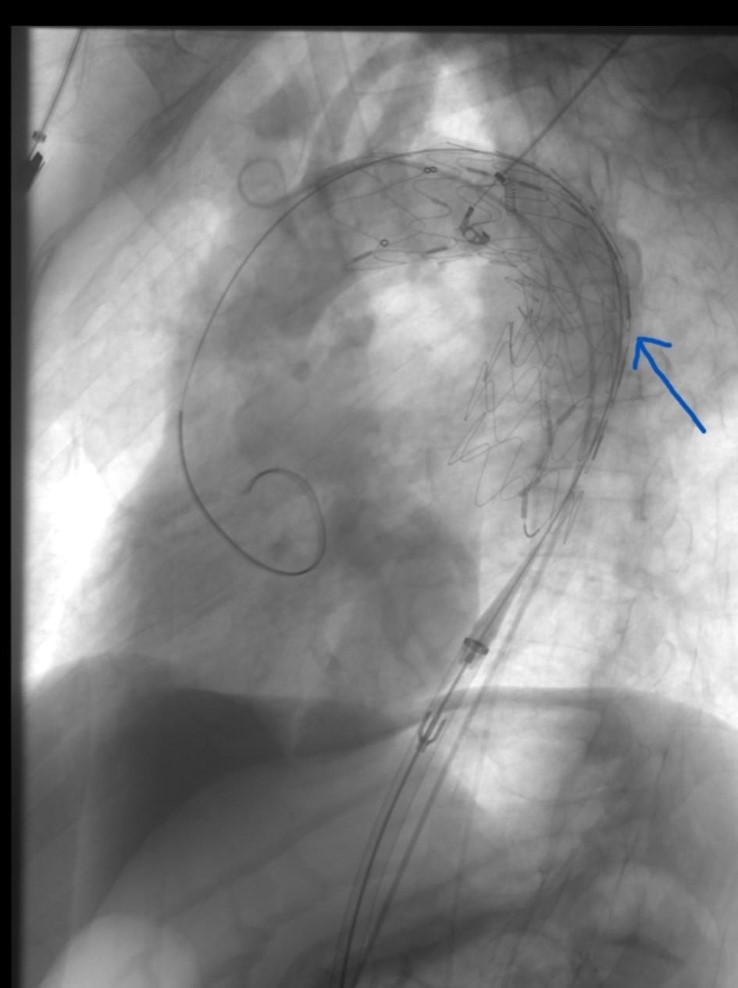

Karaman'da göğüs ve karın bölgesinde Aort denilen en büyük atardamarın balonlaşması nedeniyle hastaneye yatırılan 65 yaşındaki A.B.Ç isimli bir hastaya eşzamanlı olarak hem göğüs hem de karın bölgesindeki balona açık cerrahi uygulamadan kapalı olarak başarılı şekilde müdahale edildi.Konuyla ilgili olarak Kalp Damar Cerrahisi uzmanlarından Op. Dr. Sencer Kılıç ve Dr. Öğr. Üyesi Osman Yaşar Işıklı yapmış oldukları açıklamalarda şu ifadeler yer verdiler:"Aort denilen vücudumuzun en büyük atar damarın karın bölgesindeki balonlaşması genellikle herhangi bir yakınmaya neden olmadan sessizce genişler ve patlamaya yol açar. Bu durumdan muzdarip hastanın %80 i kaybedilir. Ameliyata ulaşmış hastalarında riski yüksektir. Kanamaya yol açmış tüm hastaların en çok %10 ile 20 si taburcu olmaktadır. Risk altındaki kişilerin anevrizma olup olmadığı önceden saptanabilirse cerrahi ya da endovasküler (TEVAR /EVAR) girişim ile yaşam tehlikesi ortadan kalkar. Sigara ve genetik faktörler balonlaşmada rol oynar.65 yaş ve üzeri grupta her 65 erkekten birinde bu hastalık görülür. Erkeklerde bayanlardan 5 kat daha sık görülmektedir. Ülkemizde her yıl 3500 ile 4000 arası kişide tehlikeli balonlaşma olduğu tahmin edilmektedir.65 yaş ve üzeri erkekler kalp ve damar cerrahisi uzmanına başvurması gerekir. Sigara içiliyorsa veya ömür boyunca 5 paketten fazla içildi ise ailede bu hastalığa sahip olanlar varsa risk daha yüksektir. Basit görüntüleme yöntemleri ile ana damarlarda balonlaşma olup olmadığı saptanabilir. Her balonlaşma girişim gerektirmeyebilir. Damar çapına göre takip edilebilir veya girişim yapılabilir. Çok geniş balonlar açık ya da kapalı yöntemlerle tedavi edilebilir. Hangi yöntemin seçileceğine; kişinin yaşına önemli sağlık sorunların olup olmamasına balonlaşma yerine göre karar verilir.5 yıl önce Türk Kalp ve Damar Cerrahisi Derneği “İçimizdeki Balon” başlıklı halkı bilinçlendirme kampanyası başlatmıştı Karaman’da da son 5 yıldır bu tür balonlaşmalara başarılı şekilde hem açık hem kapalı müdahale edilmektedir. En son 1 hafta önce hem karnında hem de göğsünde tehlikeli balonlaşma görülen A.B.Ç isimli, 65 yaşındaki hastamıza eş zamanlı hem göğüs hem de karın bölgesindeki balona açık cerrahi uygulamadan kapalı olarak başarılı şekilde müdahale edildi. Bu gün ise hastanın taburcu edilmesi planlanmaktadır. Ülkemizde sayılı kliniklerde Kalp Damar Cerrahisi, Girişimsel Radyoloji ve kimi zaman Kardiyoloji tarafından bu tür işlemler yapılmaktadır. Anestezi ve Reanimasyon Uzmanlarından Dr. Öğr. Üyesi Tayfun ET, Uzm. Dr. Mehmet Serdar Şencan ve Beyin Cerrahisi uzmanlarından Op. Dr. Gökhan Reşitoğlu’nun desteği ile anjio odasında kısa sürede gerçekleştirilen hem TEVAR hem de EVAR yöntemi ile eş zamanlı uygulanan endovasküler işleminin Kalp Damar Cerrahları tarafından Karaman’da uygulanabiliyor olması hastamız için büyük şanstır. Geç kalmış olsa da yıllardır kullandığı sigarayı bırakmış olan hastamıza uzun ömürler diliyoruz."Böyle nitelikli ve özellikli ameliyatların Karaman Eğitim ve Araştırma Hastanesinde başarıyla yapıldığını aktaran Karaman Eğitim ve Araştırma Hastanesi Başhekimi Doç. Dr. Halil İbrahim TAŞCI, “ ilimizde bu tür ameliyatın yapılmasının gururunu yaşıyoruz. Hastanemiz bu tür ameliyatları yapma imkânına ve teknik donanıma sahiptir. Bundan sonra da bu tür ameliyatları gerçekleştirmeye devam edeceğiz. Bu ameliyatı gerçekleştiren hekimlerimize ve ekibine çok teşekkür ediyorum." ifadelerini kullandı.

Cerrahi ile teknolojinin birlikte kullanıldığı ve Türkiye’de az sayıda merkezde yapılabilen özellikli ve nitelikli ameliyatlardan Aort Anevrizması tedavisi Karaman Eğitim ve Araştırma Hastanesi'nde başarıyla yapıldı.